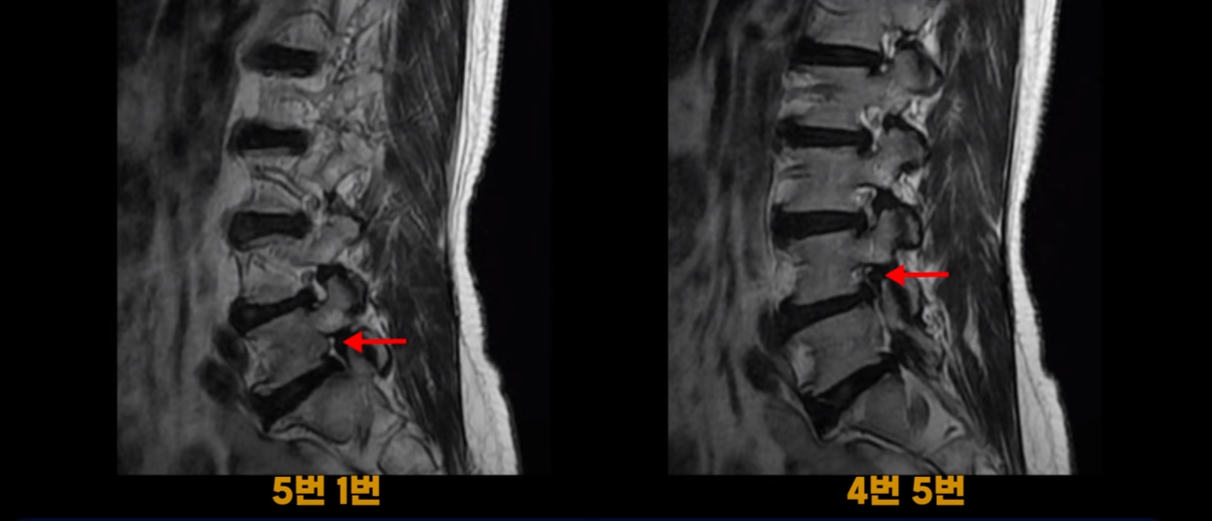

하지만 이 디스크 파열은 오래된 걸로 보이며, 지금 이 환자분의 아픈 양쪽 다리 특히 양쪽 발의 통증, 발 시린 증상과는 관련이 없어 보입니다. 오른쪽 왼쪽의 신경가지가 빠져나가는 추간공을 보면 오른쪽은 5번 1번과 4번 5번이 많이 좁아져 있고

왼쪽은 5번 1번이 많이 좁아져 있습니다.

이렇게 오른쪽 왼쪽 양쪽 추간공들이 다 좁아져 있고 신경가지들이 눌려있으니까 양쪽다리와 양쪽 발이 저리고 시리고 아파서 걷기 어렵습니다. 그런데 이 환자분은 신경주사를 여러 번 맞아도 듣지를 않는데요. 이렇게 신경주사가 듣지 않으면 십중팔구 수술밖에 방법이 없다는 얘기를 듣습니다. 그럼 어떻게 이런 신경이 눌려있는 환자분들을 수술 없이 치료해서 잘 걷게 만들고 다리와 발이 저리고 시리고 아픈 증상이 사라지게 만들까요? 지금부터 설명해드립니다.